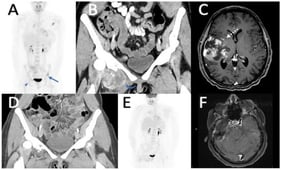

Background/Objectives: Radioactive iodine (RAI) therapy is widely used to treat metastatic differentiated thyroid cancer. To investigate physiological determinants of treatment response, a mechanistic model was developed, formulated as a system of coupled ordinary differential equations. Methods: The model captures the interactions between tumor burden, thyroglobulin (Tg) production and clearance, and radioactive iodine activity within a pharmacokinetic–pharmacodynamic framework. Model parameters were estimated using the Monte Carlo Stochastic Approximation Expectation–Maximization (MCMCSAEM) algorithm, based on clinical data from a cohort of 50 patients. Results: Tumor radiosensitivity (ρ) and initial tumor burden (N0) consistently emerged as the most influential factors in both responder and non-responder groups classified by disease doubling time under RAI (Td). A reduced model using only these two parameters preserved the principal response patterns of the full model. Other parameters influenced transient dynamics but had limited effect on overall Tg variance. Conclusions: These results support the use of a reduced calibration approach focused on ρ, N0, and the effective doubling time Td. The findings establish a theoretical foundation for developing tractable dynamic surrogates that reproduce the main treatment kinetics and support model-based clinical decision-making in RAI therapy.